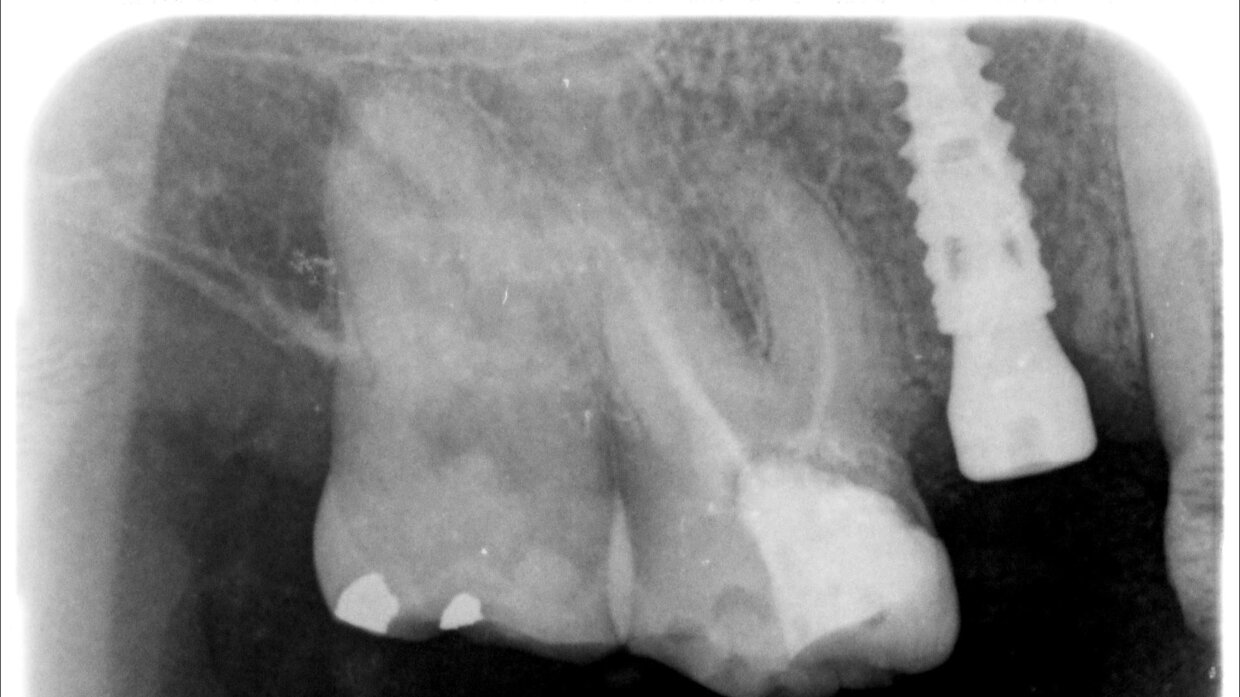

Il posizionamento degli impianti è stato pianificato prima dell'intervento su un software dedicato. In un'unica seduta, dopo l'estrazione degli elementi dentari compromessi, sono stati immediatamente inseriti gli impianti nella posizione pianificata, grazie alla realizzazione della dima chirurgica. Per ridurre il riassorbimento osseo a lungo termine e garantire quindi una maggiore resa estetica (vista la zona d'intervento), la chirurgia è stata eseguita con una particolare tecnica denominata: Socket Shield Technique.